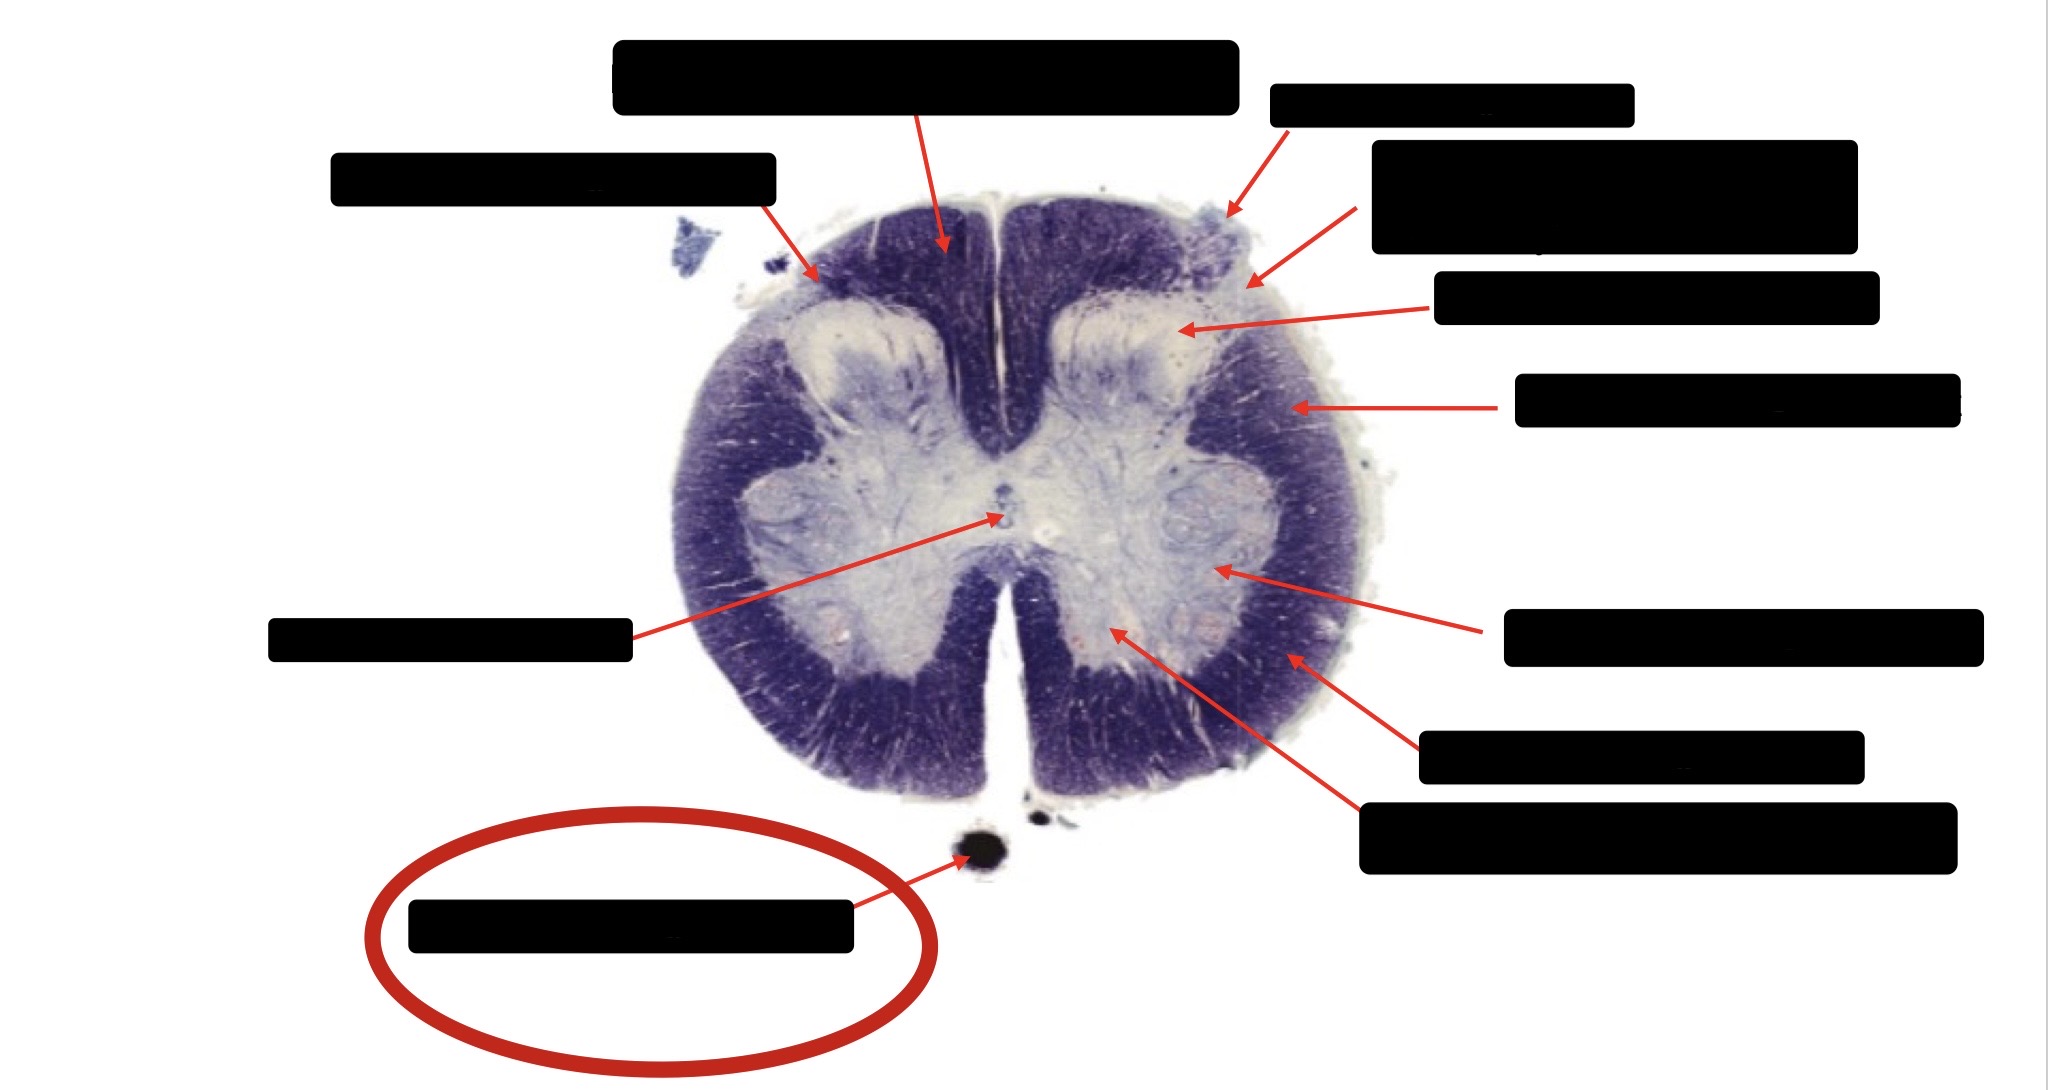

Posterior Column (Fasciculus Gracilis)

Spinothalmic Tract

Posterior Column (Fasciculus Cuneatus)

Substantia Gelatinosa

Anterior Horn Motor Neurons (Distal Muscles)

Anterior Horn Motor Neurons (Proximal Muscles)

Ventral Root Fibers

Central Canal

Anterior Corticospinal Tract

Large Fiber Entry Zone

Dorsal Rootlet

Posterior Spinocerebellar Tract

Lateral Corticospinal Tract

Anterior Spinocerebellar Tract